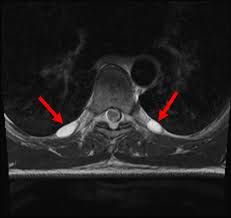

Surgeons carefully remove your schwannoma while taking care to preserve nerve fascicles that arent affected by your tumor. Rarely nerve sheath tumors can be malignant. On conventional MRI and diffusion-weighted imaging DWI MPNSTs and BPNSTs showed significant differences in tumor size margin presence of perilesional edema and absence of split fat fascicular.

On conventional MRI and diffusion-weighted imaging DWI MPNSTs and BPNSTs showed significant differences in tumor size margin presence of perilesional edema and absence of split fat. View chapter Purchase book.

Results of this limited experience indicate linear acceleratorbased spinal radiosurgery is feasible for treatment of benign nerve sheath tumors. Most benign nerve sheath tumors need no treatment other than observation which involves following up with repeat physical examinations and serial imaging. This of course means that surgery is required. On conventional MRI and diffusion-weighted imaging DWI MPNSTs and BPNSTs showed significant differences in tumor size margin presence of perilesional edema and absence of split fat fascicular. Some nerve sheath tumors are treated with surgery. On conventional MRI and diffusion-weighted imaging DWI MPNSTs and BPNSTs showed significant differences in tumor size margin presence of perilesional edema and absence of split fat. Rarely nerve sheath tumors can be malignant.